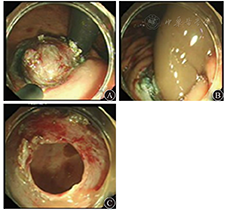

患者女,18岁,因上腹胀6个月于2013年9月23日入院。体检未见明显异常。胃镜检查示胃底近齿状线可见黏膜隆起,大小约3.0 cm×4.0 cm,表面光滑,颜色同周围黏膜(图1),胃镜通过贲门未感明显阻力。超声内镜示胃壁层次结构清晰完整,病变起源于黏膜下层,边界尚清,内部见均匀中等偏高回声,切面大小为3.4 cm×2.4 cm(图2)。胃二期增强CT检查示胃底近齿状线处胃腔外见结节状低密度影,直径大小约3.8 cm(图3),增强扫描边缘轻度强化。在内镜下标记病变后行黏膜下注射,剥离肿物表面黏膜,暴露黏膜下病变,病变触之尚软,表面见纤维膜包裹,切开后见咖啡色黏稠液体流出,充分引流及灌洗后切除部分囊壁送病理检查,并开放囊腔(图4),手术顺利,术后7 d出院。病理诊断为胃黏膜下囊性淋巴管瘤;HE染色见扩张的淋巴管成囊状,并见少许腺体成分及平滑肌组织增生;免疫组织化学检查结果为结蛋白、CD31、CD34、细胞角蛋白(cytokeratin,CK)20、Ki67、H.pylori阴性,特异性淋巴管内皮标志物D2-40(图5)、CK7阳性。术后5个月复查胃镜,未见复发(图6)。